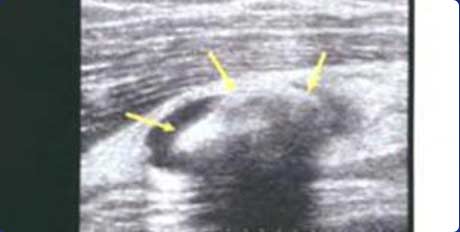

回声伴声影

膝关节髌上囊扩张积液,可见团状强回声,并伴声影